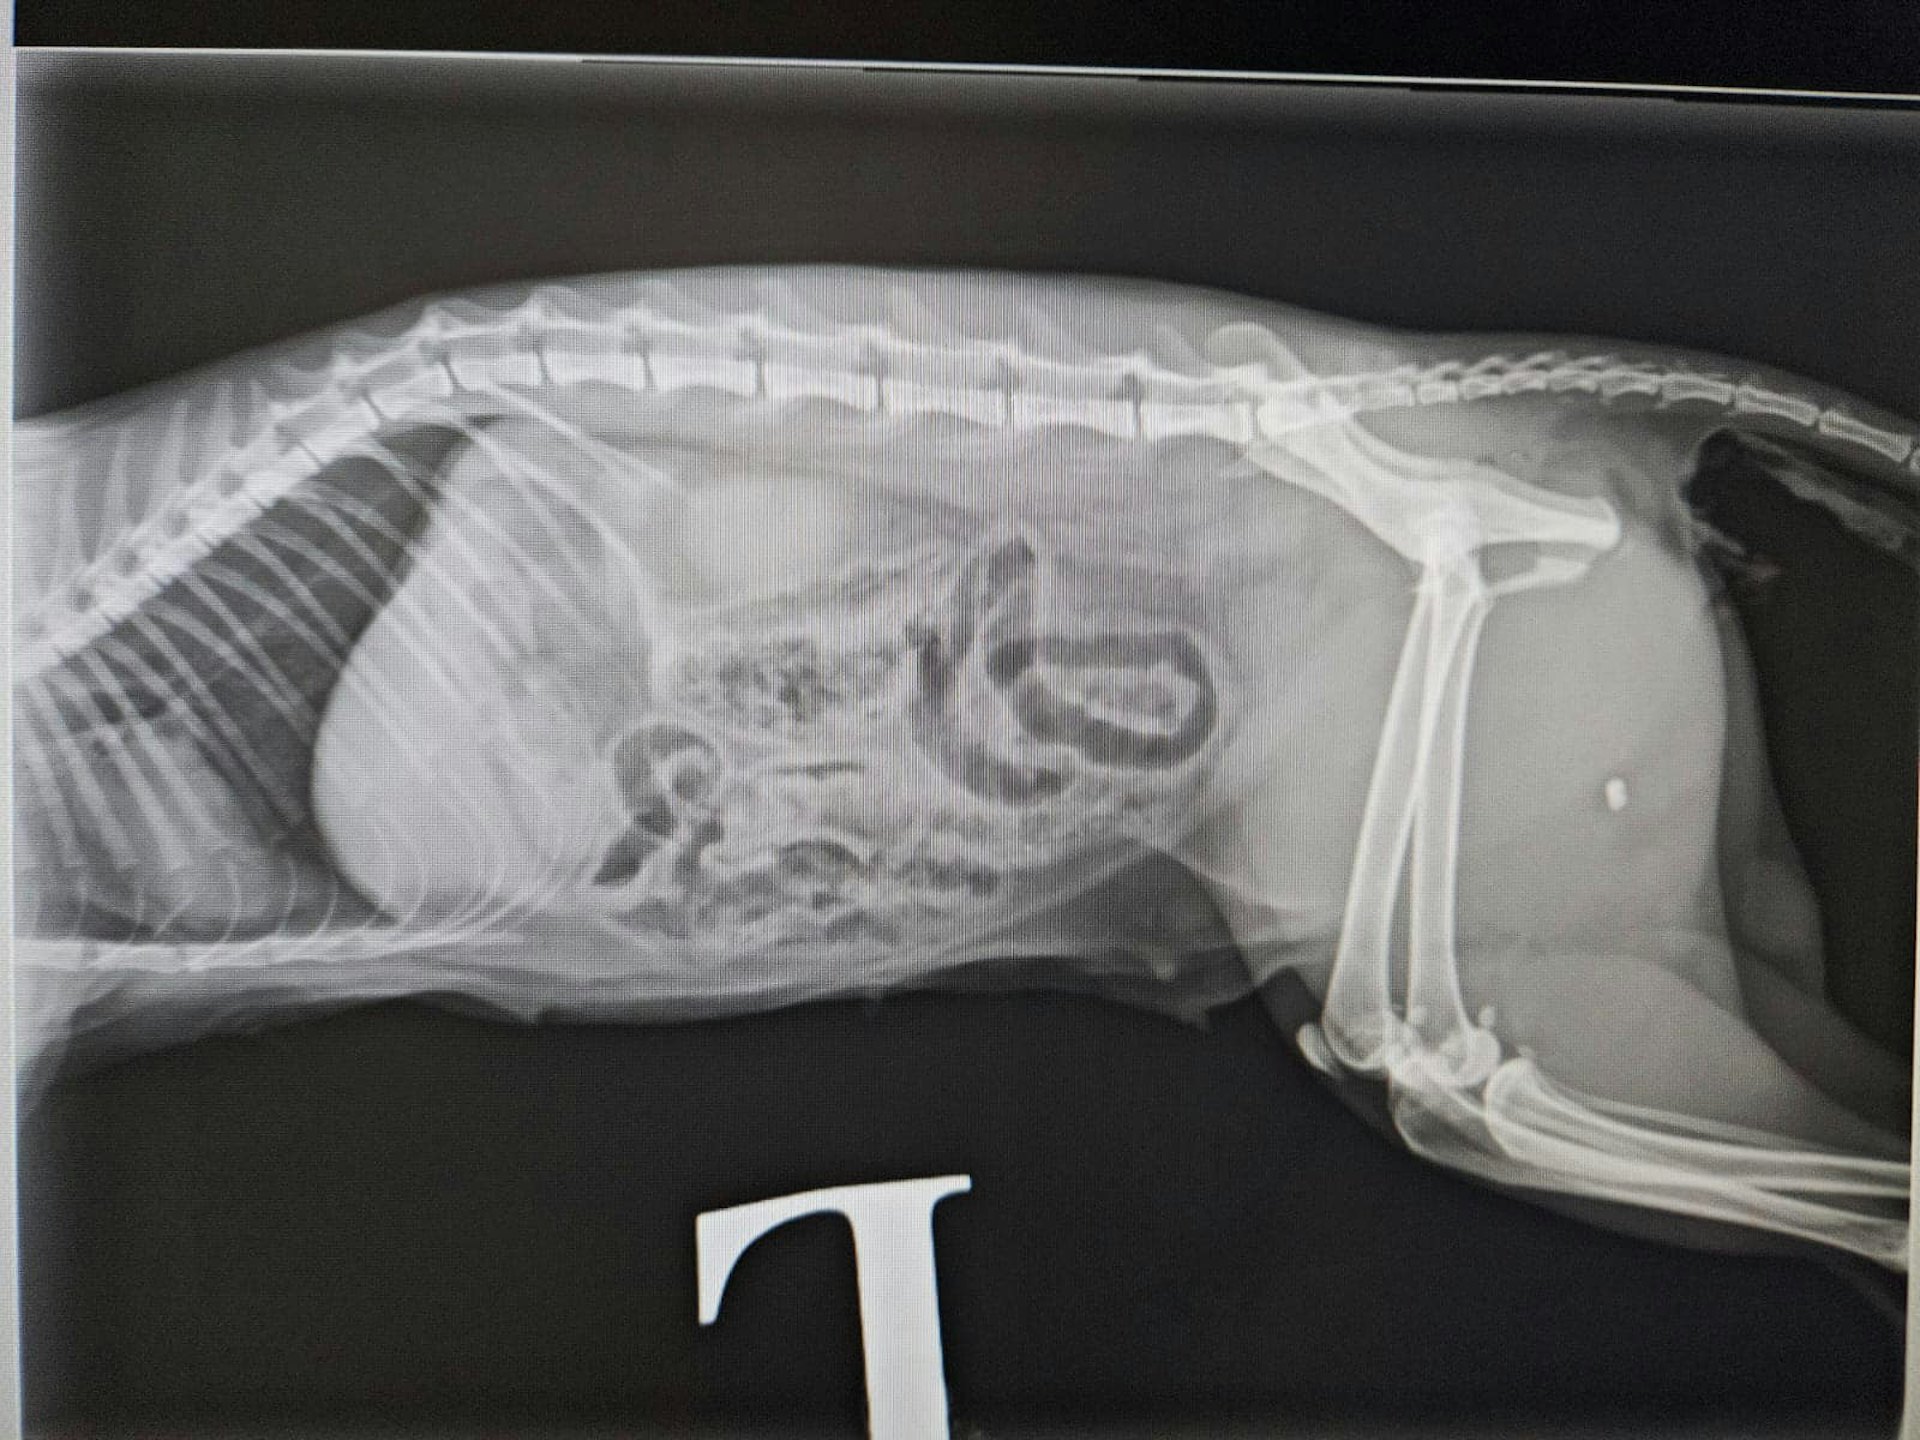

受傷貓隻接受X光檢查。(facebook專頁「毛守救援」圖片)